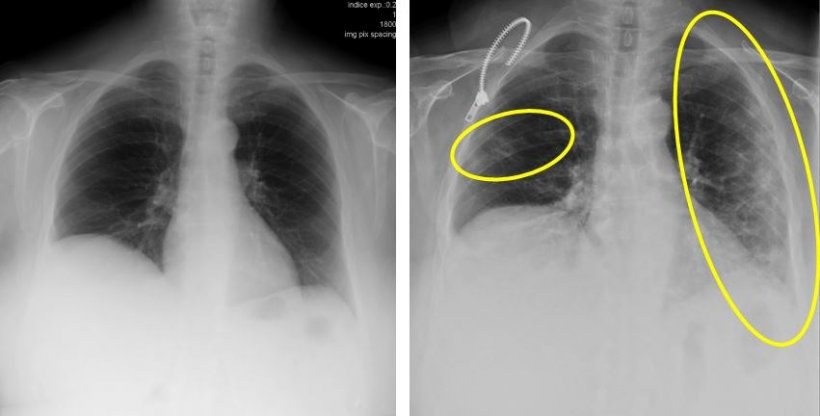

At the time of writing this project the Sars-CoV-2 virus and the associated disease COVID-19, poses a great threat to mankind. The main diagnosis tool, the PCR test, has proven extremely helpful, but requires an appropriate lab and trained personnel. A complimentary tool could be medical imaging techniques that are widely available, even in remote areas. If COVID-19 could be diagnosed with a simple X-Ray image, the time between suspecting COVID-19 and entering quarantine could be substantially reduced. However, as in many medical imaging applications of machine learning, generating large dataset is challenging, especially under privacy aspects. Therefore, we focus on data efficiency and how to learn from large bodies of only remotely related data.